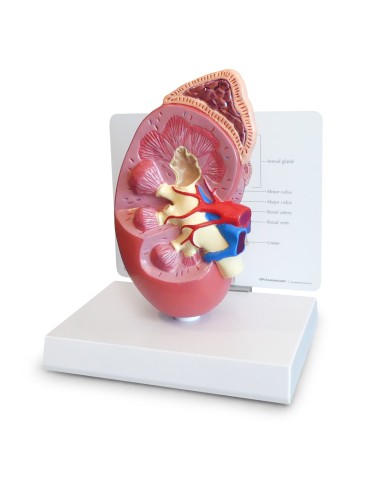

Questo e tanto altro ancora trovi nella sezione dedicata ai modellini anatomici, occhi, denti, orecchio, naso e gola, e i modelli anatomici per ostetricia e ginecologia, per lo studio dell'anatomia della pelvi e del bacino umano.

I modelli anatomici didattici sono riproduzioni di strutture anatomiche perfettamente uguali a quelle vere, i modelli di ossa sono realizzati dalla scansione di ossa vere, l'esperienza tattile è assolutamente realistica, ed anche il peso delle ossa corrisponde all'incirca al peso delle ossa vere.

Gli studenti di medicina utilizzano i modelli anatomici per i loro studi di anatomia umana, studiare l'anatomia sui libri non basta, un modellino anatomico permette uno studio molto più accurato che una foto o un disegno su un libro.

Medici, fisioterapisti, osteopati e professionisti sanitari utilizzano i modelli anatomici per dare spiegazioni ai pazienti sulle patologie, risparmiando tanto tempo prezioso durante la spiegazione, che diventa molto più efficace.